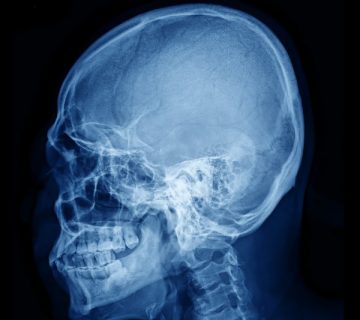

La reconstrucción facial engloba al conjunto de técnicas quirúrgicas destinadas a recuperar el aspecto y funciones del rostro perdidos tras un accidente o la extirpación de un tumor de cabeza y cuello. Exige el dominio de múltiples procedimientos reconstructivos, desde los más sencillos como un injerto de piel hasta procedimientos mucho más complejos que demandan la participación de diferentes especialistas.

Cada rostro es único y está caracterizado por una estructura ósea y dental determinada y una cobertura de partes blandas (piel, músculos y grasa) que varía con la edad. La cara determina en parte nuestro carácter y es el principal órgano de expresión de nuestras emociones. Es así que un procedimiento de este tipo, dependiendo el caso, podría demandar múltiples consideraciones de importancia, como son la estética, funciones localizadas en el área como la masticación, el habla, la mímica, la visión, el olfato y la audición, entre otras.